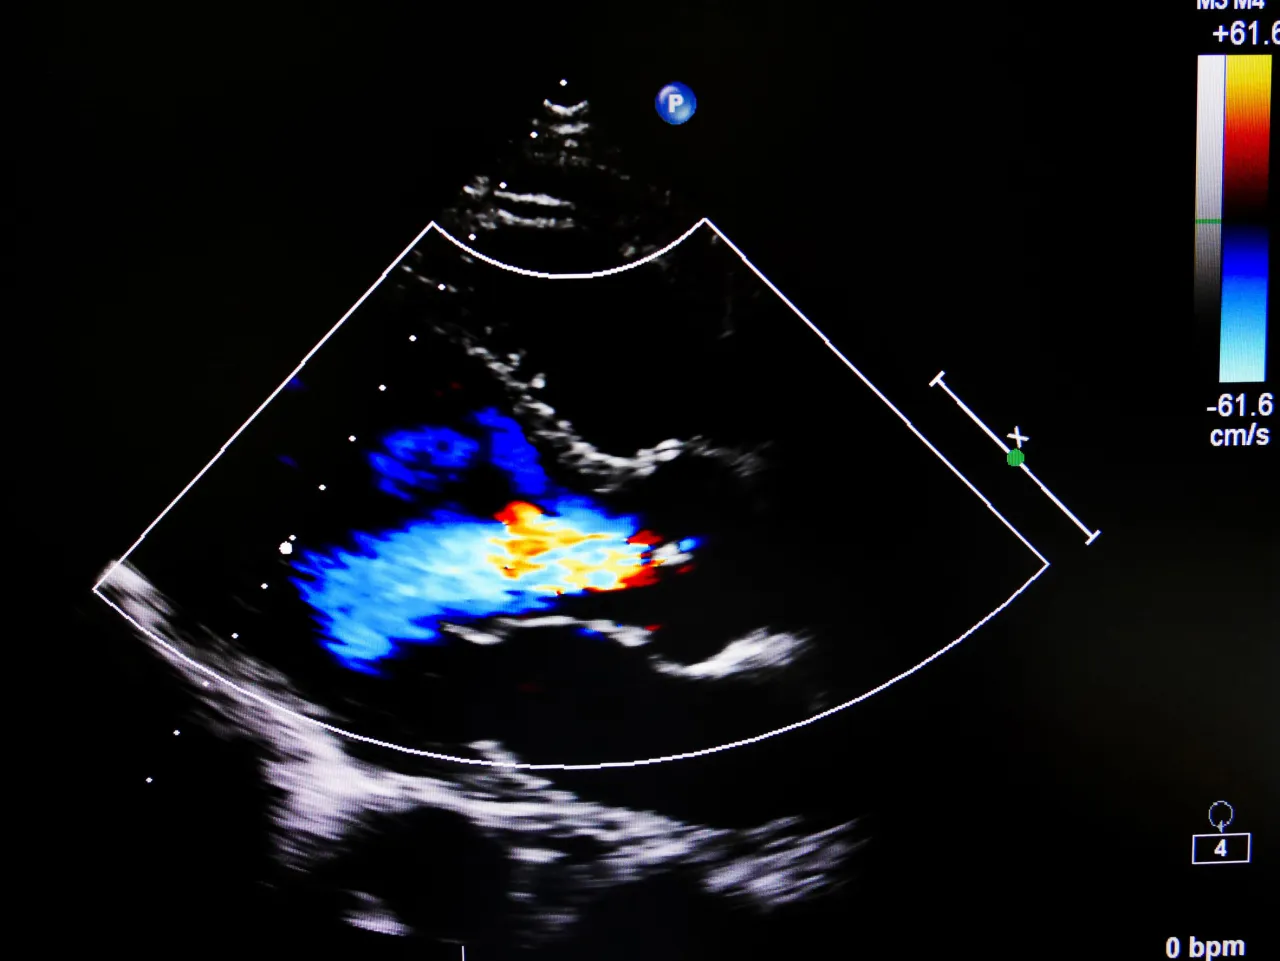

Samo badanie jest nieinwazyjne, bezbolesne i całkowicie bezpieczne. Zazwyczaj trwa od 15 do 40 minut, w zależności od zakresu badania i złożoności przypadku. Pacjent proszony jest o odsłonięcie nóg i położenie się na kozetce. Lekarz nałoży na skórę specjalny żel, który ułatwia przewodzenie fal ultradźwiękowych i przesuwanie głowicy aparatu USG. Głowica ta emituje fale, które odbijają się od przepływającej krwi, a następnie są przetwarzane na obraz widoczny na monitorze.

Podczas badania lekarz będzie oceniał przepływ krwi w żyłach, stan zastawek oraz ewentualną obecność zakrzepów. Może prosić Cię o zmianę pozycji (np. położenie się na brzuchu) lub wykonanie prostych manewrów, takich jak uciśnięcie łydki czy wstrzymanie oddechu, aby ocenić reakcję naczyń. Cały czas będziesz mógł obserwować obraz na ekranie, choć interpretacja należy do specjalisty.